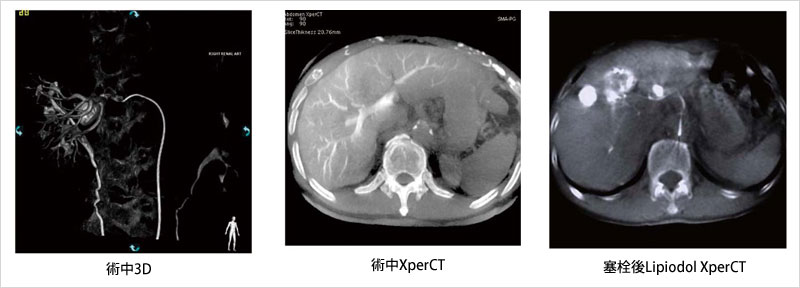

このXperCTは,血管撮影装置における回転撮影画像からコーンビームCT(CBCT)の原理を応用し,CTを使用せずに軟部組織の表示(図3)を可能にした。動静脈奇形(AVM)における血管走行の確認,プラーク性状判断,肝細胞がんにおける肝動脈塞栓療法時の肝動脈造影(CTHA),経動脈性門脈造影(CTAP)への応用が進んでいる。肝細胞がんに対する経カテーテル的肝動脈化学塞栓療法(TACE)時には,存在診断,栄養血管の同定,塞栓範囲の確認(Lipiodol CT),濃染の不明瞭な腫瘍に対する塞栓効果の確認に対し有用であり,治療中のみならずPre/Postの支援機能として期待されている。

図3 腹部XperCT画像